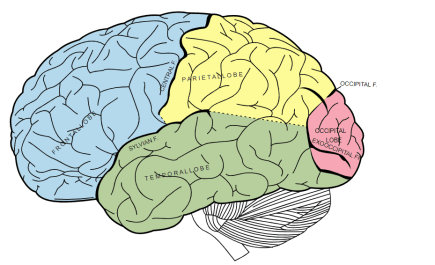

Position and anatomy of the parietal lobe

顶叶的位置和解剖

The parietal lobe is the middle part of the brain. It is located behind the central furrow towards the back. It is separated by incision preoccipitalis from the occipital lobe, lying completely posteriorly (1).

顶叶是大脑的中间部分,它位于背面中央犁沟的后面。

As already said, the parietal lobe occupies the upper side of the hemisphere. The parietal lobe limits from the anterior and lateral sides include the area from the front to the central sulcus, from the temporal floor to the lateral sulcus, from the occipital sulcus to the imaginary line that flows from the upper edge of the parietal occipital sulcus to the lower hemisphere edge.

如前所述,顶叶位于大脑半球的上半部。从前侧和外侧的顶叶界限包括从前面到中央沟、从颞底到外侧沟、从枕骨沟到从顶枕沟上缘到下半球边缘的假想线。

Parietal lobe syndrome implies an outbreak of function of this lobe due to damage to its structures. This lobe is located between the frontal lobes in both cerebral hemispheres. The parietal lobe extends from the central sulcus to the parieto-occipital groove separating it from the occipital lobe. It contains the primary somatosensory cortex.

顶叶综合征提示该脑叶由于结构损伤而发生功能性疾病。该脑叶位于两个大脑半球的额叶之间。顶叶从中央沟延伸至顶枕沟,将顶叶与枕叶分开。它包含初级躯体感觉皮层。